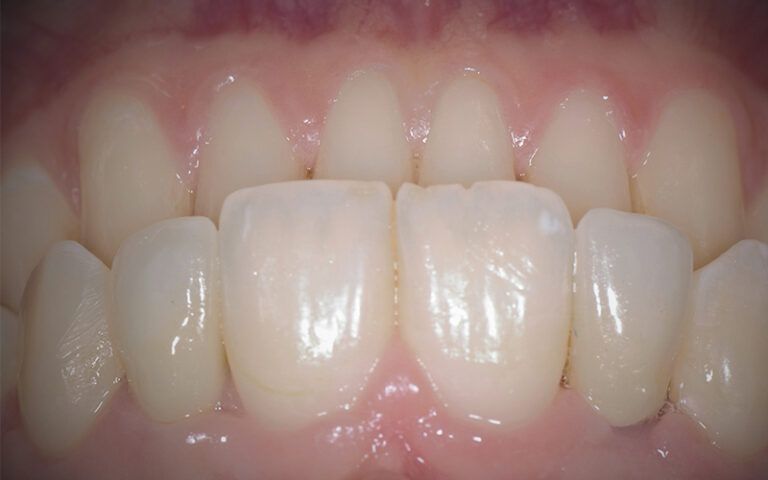

After a few days, the pertinent x-ray and clinical controls were carried out and the two crowns were definitively cemented, completing the restoration of the agenesis of the two lateral incisors 12 and 22.

Definitive Zr crowns post-load